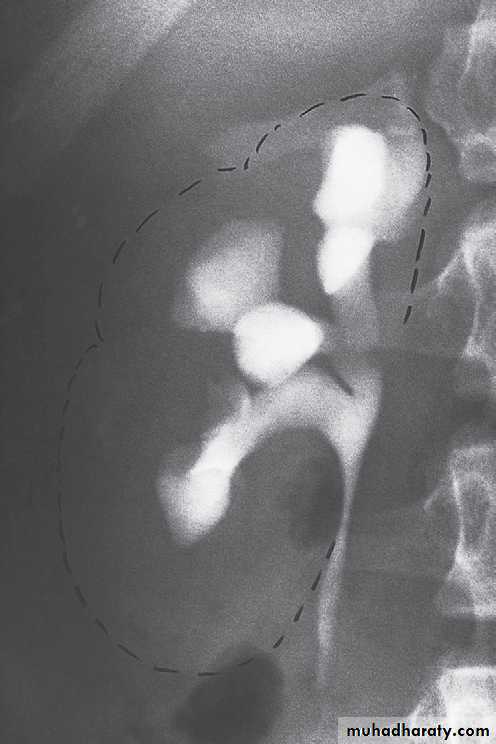

Retrograde and antegrade pyelographyThe techniques of retrograde and antegrade pyelography (the term pyelography means demonstrating the pelvicaliceal system and ureters) involve direct injection of contrast material into the pelvicaliceal system or ureters through catheters placed via cystoscopy (retrograde pyelography) or percutaneously into the kidney via the loin (antegrade pyelography).

The indications are limited to those situationswhere the information cannot be achieved by less invasive means, e.g. IVU, CT or MRI to confirm a possible transitional cell carcinoma in the renal pelvis or ureter.